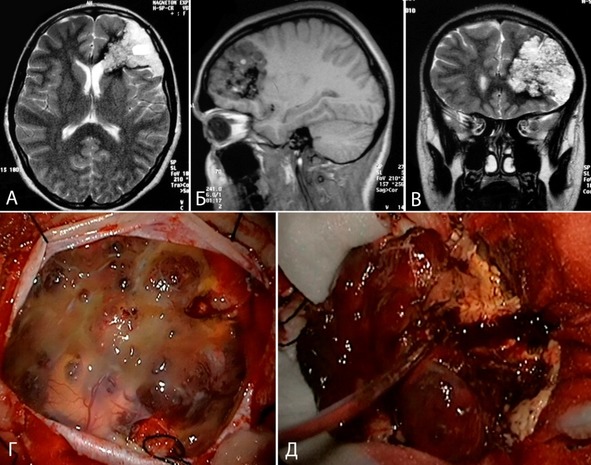

Каверномы имели различные размеры, варьировавшие от нескольких миллиметров до 9 см (рисунок 12). Средний размер каверномы составил 2,6±1,5 см, медиана – 2,2 [1,5;3,5]. Из анализа были исключены каверномы IV типа ввиду невозможности точно указать размер и отсутствия четких представлений о природе этих образований. Это, скорее всего, явилось причиной несоответствия распределения каверном нормальному (диаграмма на рисунке 13).

Рисунок 12. Крупная кавернома левой лобной доли (до 9 см в диаметре): А – МРТ Т2 взвешенное изображение в аксиальной проекции, Б – МРТ Т1 взвешенное изображение в сагиттальной проекции, В – МРТ Т2 взвешенное изображение во фронтальной проекции, Г – интраоперационная фотография на этапе после вскрытия ТМО, Д – интраоперационная фотография на этапе выделения каверномы en block.